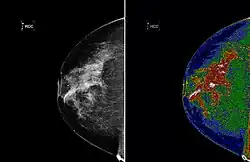

A region of interest (often abbreviated ROI) is a sample within a data set identified for a particular purpose.[1] The concept of a ROI is commonly used in many application areas. For example, in medical imaging, the boundaries of a tumor may be defined on an image or in a volume, for the purpose of measuring its size. The endocardial border may be defined on an image, perhaps during different phases of the cardiac cycle, for example, end-systole and end-diastole, for the purpose of assessing cardiac function. In geographical information systems (GIS), a ROI can be taken literally as a polygonal selection from a 2D map. In computer vision and optical character recognition, the ROI defines the borders of an object under consideration. In many applications, symbolic (textual) labels are added to a ROI, to describe its content in a compact manner. Within a ROI may lie individual points of interest (POIs).

Medical imaging

Medical imaging standards such as DICOM provide general and application-specific mechanisms to support various use-cases.

- Pixels (possibly non-contiguous) may be classified into segments encoded in a segmentation object as either binary or probabilistic values in a raster (which is not required to have the same spatial sampling or extent as the images from which the segmentation was derived); these are usually referenced by other objects containing structured content (structured reports)